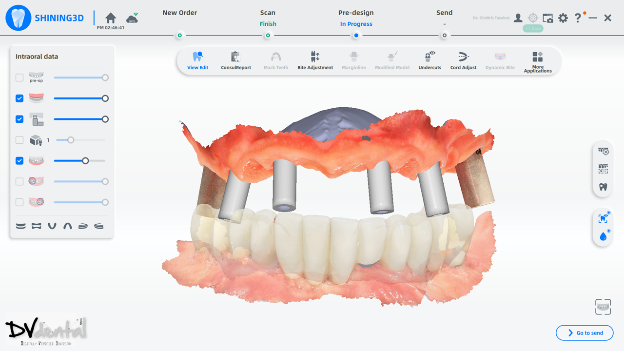

1. Aoralscan Elite to capture all-on-six impression data

For occlusal reconstruction cases, precise data are the foundation of success. The intraoral scanner Aoralscan Elite’s IPG technology can provide sub-millimeter accuracy, ensuring the passive fit of the prosthesis, particularly in edentulous implant-supported restoration cases.

In this case, we encountered a problem: while the MUA of the four anterior implants were compatible with the IPG scan bodies, the two posterior implants were not compatible with the IPG scan bodies. Therefore, we will scan the two posterior implants using normal 3D reconstruction technology (in the soft tissue scan, placing two standard scan bodies on the MUA of the two posterior implants) and then scan the anterior implants with IPG technology (placing the IPG scan bodies on the MUA of the four anterior implants).

In the next stage, alignment between the IPG scan bodies and the soft tissue, along with the standard scan bodies, will be performed to obtain a digital model with six scan bodies of the Implants.

To achieve more precise occlusion, in the final step of the scanning process, Aoralscan Elite can help us capture the dynamic bite, which can be imported into the design software for subsequent dynamic occlusal design.

Fig 11,12: Step 6, install and scan the coded scanbody using photogrammetry technology